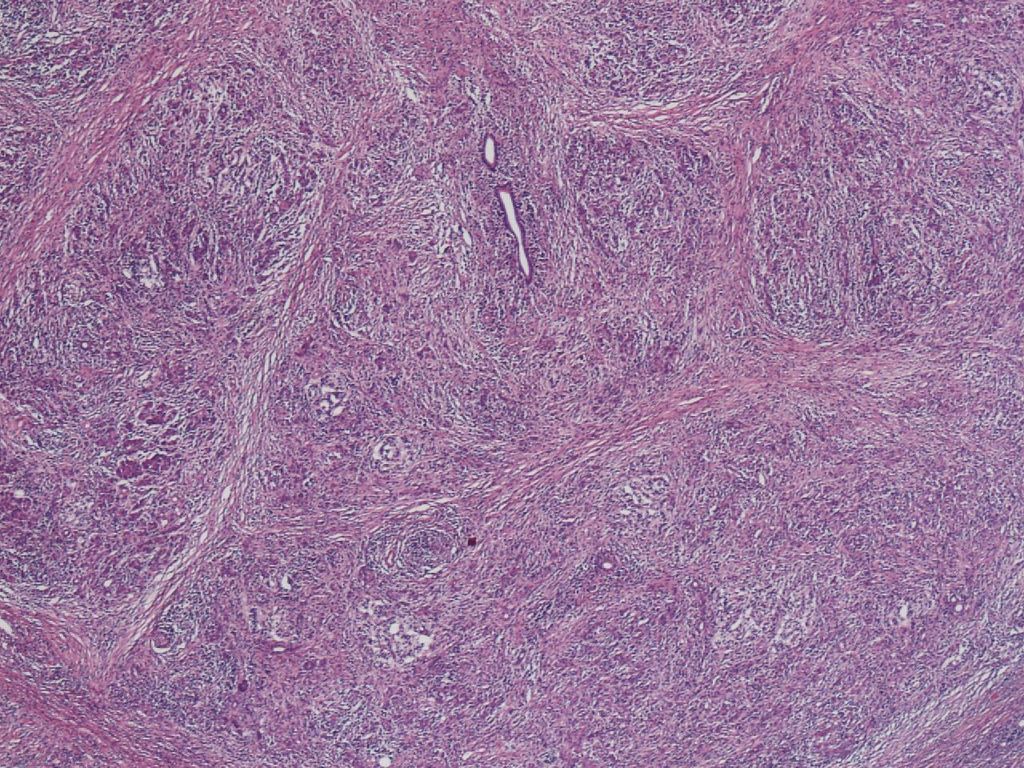

Storiform Fibrosis

Storiform fibrosis is a peculiar fibrosing lesion seen in almost all cases of type 1 AIP. It is not the uniform streaming pattern commonly seen in other chronic inflammatory diseases. Instead storiform fibrosis is characterized by a haphazard and typically swirling pattern. Similar to granulation tissues changing into fibrosis over time, a series of histological differences in storiform fibrosis can be appreciated. In the early stage, a cellular component of small spindle cells, lymphocytes and plasma cells predominates, with little collagen formation (cell-rich type; Figure 2a).Collagen formation then gradually proceeds, and the cell component decreases (transitional type; Figure 2b), until finally fibrotic foci consisting mostly of collagen with a scanty cell component develop (fibrotic type; Figure 2c). A mixture of various stages may be seen in a single case.

Figure 2a. Storiform fibrosis of Type 1 AIP. Cell-rich type.

Figure 2b.Transitional type Figure 2c. Fibrotic type